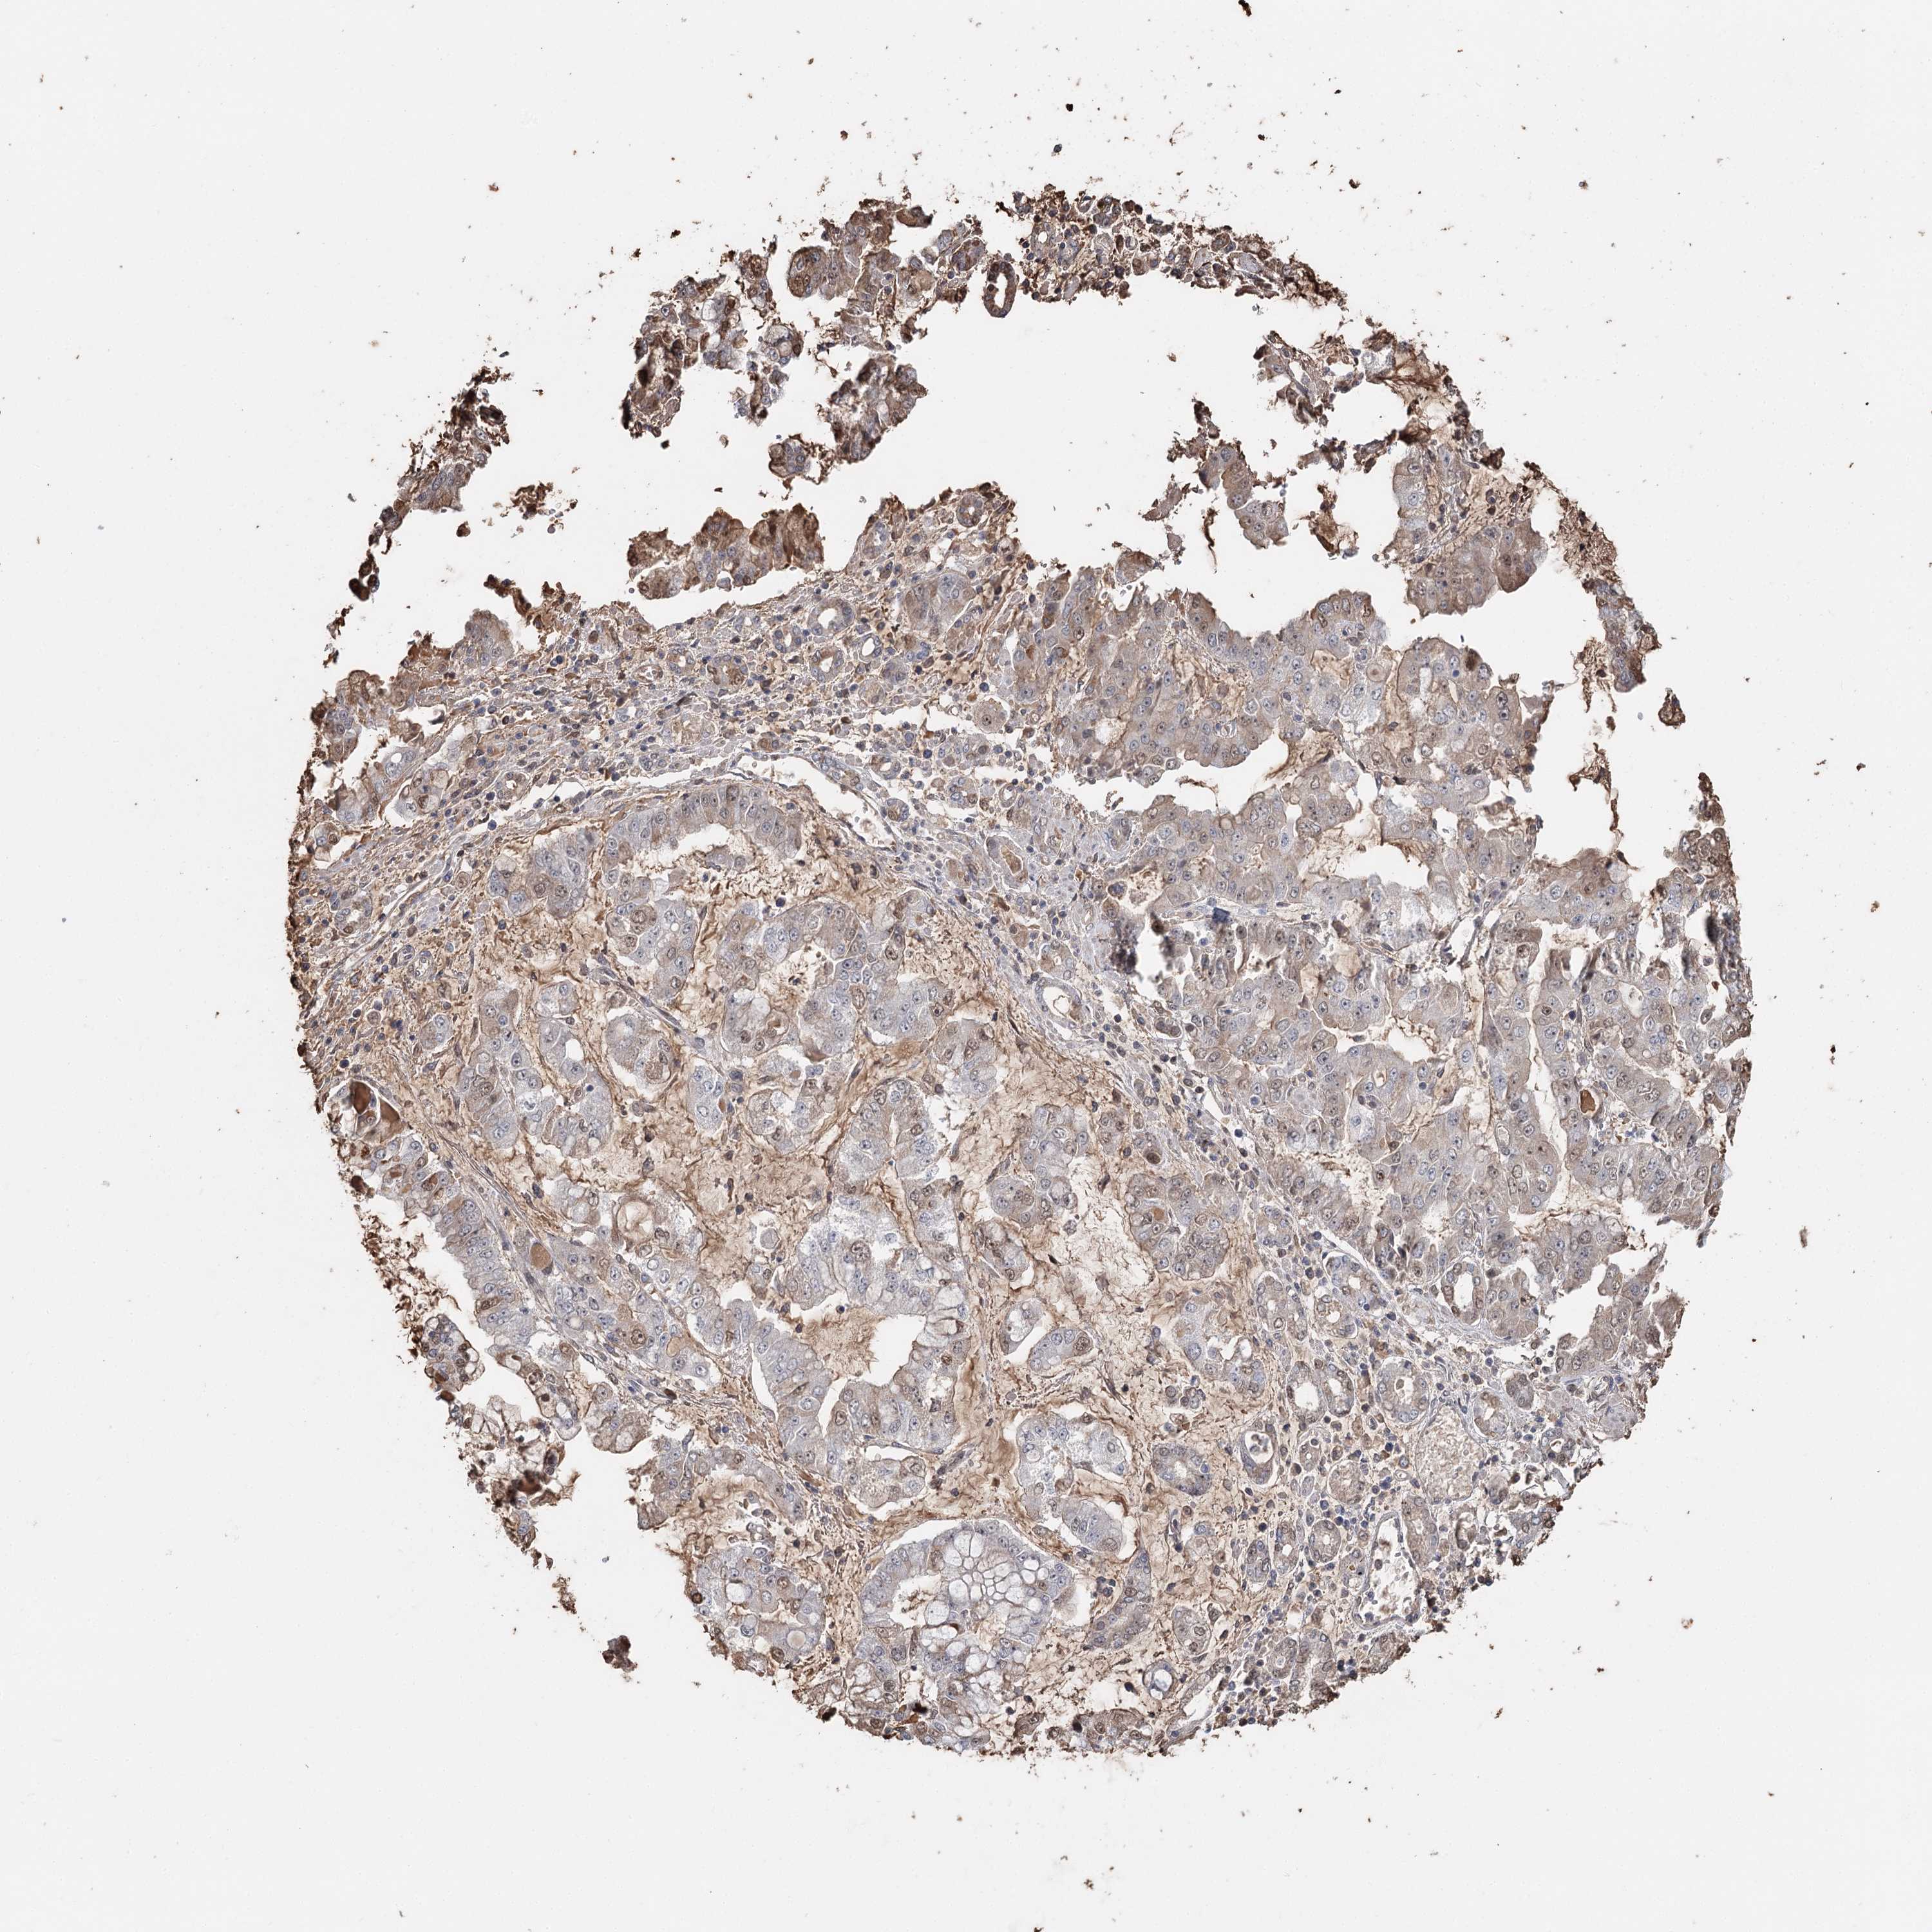

STOMACH CANCER - Protein expressioni

A mouse-over function shows sample information and annotation data. Click on an image to view it in a full screen mode. Samples can be filtered based on level of antibody staining by selecting one or several of the following categories: high, medium, low and not detected. The assay and annotation is described here.

Note that samples used for immunohistochemistry by the Human Protein Atlas do not correspond to samples in the TCGA dataset.

Antibody stainingi

Antibody staining in the annotated cell types in the current human tissue is reported as not detected, low, medium, or high, based on conventional immunohistochemistry profiling in selected tissues. This score is based on the combination of the staining intensity and fraction of stained cells.

Each image is clickable and will lead to virtual microscopy that enables deeper exploration of all samples and also displays staining intensity scores, fraction scores and subcellular localization as well as patient and tissue information for each sample.

Antibody HPA005480

Antibody HPA024300

Antibody CAB037030

Staining

High

Medium

Low

Not detected

Intensity

Strong

Moderate

Weak

Negative

Quantity

>75%

75%-25%

<25%

None

Location

Nuclear

Cytoplasmic/membranous

Cytoplasmic/membranous,nuclear

Adenocarcinoma, NOS

Adenocarcinoma, High grade